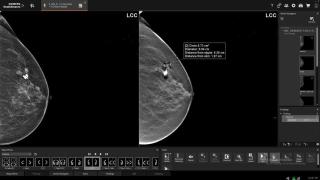

Una médico revisa una prueba de detección de cáncer de mama.

Una médico revisa una prueba de detección de cáncer de mama. EP Sevilla